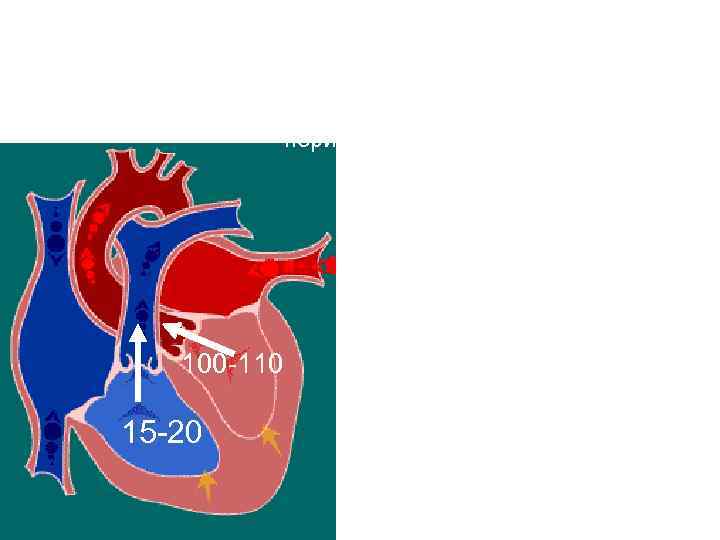

Систола желудочков Фаза изгнания период медленного изгнания Клапаны: створчатые - закрыты полулунные – открыты Давление в желудочках: -правом – 15 -20 мм рт. ст 100 -110 15 -20 - левом – 100 -110 мм рт. ст Гемодинамика: 1/3 систолического объема выбрасывается в аорту и легочный ствол В желудочках остается по 60 мл крови (конечно-систолический объем – КСО)

Систола желудочков Фаза изгнания период медленного изгнания Клапаны: створчатые - закрыты полулунные – открыты Давление в желудочках: -правом – 15 -20 мм рт. ст 100 -110 15 -20 - левом – 100 -110 мм рт. ст Гемодинамика: 1/3 систолического объема выбрасывается в аорту и легочный ствол В желудочках остается по 60 мл крови (конечно-систолический объем – КСО)